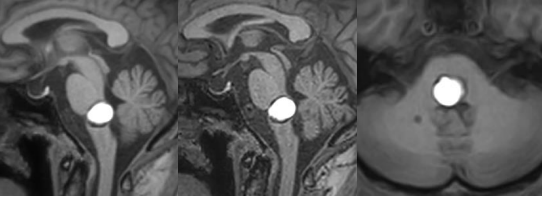

脑瘤的头痛有什么特点?

一是排除了感冒,头部外伤及头部邻近器官的炎症而以迁延性头部胀痛或钝痛;或为间歇性,或为阵发性,多无定位定点,可波及全脑沉重不适,且逐渐加重,与时俱进。头痛渐重渐频的原因,是因为肿瘤在不断增大,颅内压力不断增高的缘故。恶性脑瘤因生长快且有毒素作用,脑水肿较重。头痛症状更明显;靠近脑室的肿瘤,因常影响脑脊液循环,故头痛,头重常是一位的症状。

二是头痛可以全天候发作,但多在清晨明显,且在低头、咳嗽、喷嚏、排便时往往加重,头抬高、坐位或站立时减轻。老年人因多有脑萎缩,颅缝尚未闭合,所以,颅内空间压有较大的缓冲区,所以老人、幼儿的脑瘤头痛则比较缓慢和较轻,因此较易延误诊断。三是脑瘤的中、晚期,头痛常伴有呕吐及视物模糊,头痛越重,呕吐越多,且呕吐多为突发喷射状呕出,与食物无关,多见空腹,无恶心、胃痛。视物不清是渐进性的,多为双眼同侧,午后较重,与近视、疲劳无关。这是因颅内压增高影响眼睛的血液循环所致。若用眼底镜观测,则可见眼底水肿或出血。

另外,虽然脑瘤患者头痛多,但单靠头痛是无法确诊脑瘤的,它只能作为一种警示。同时,头痛也不能作为脑瘤的定位和定性,并不是说头顶部痛就说肿瘤在痛点这里。诊断脑瘤绝没那么简单,还得综合其他症状、体征,如失落、偏瘫、癫痫、精神障碍、平衡的失调,颅神经损害等来分析判断。